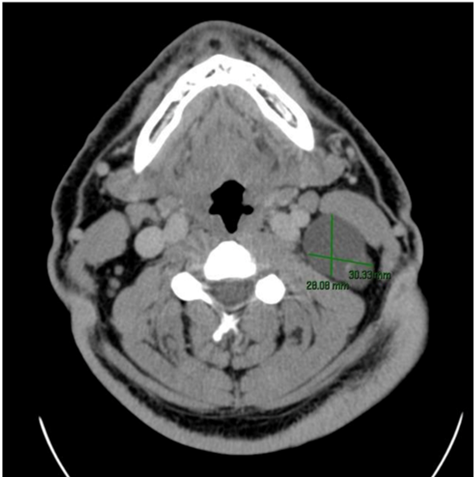

A contrast-enhanced cervical CT study was performed that described a polylobulated lesion with a cystic component and punctate calcification measuring 28 x 33 mm located in the left laterocervical region (area IIB) associated with a 12 x 13 mm level III left cystic adenopathy (Figure 1).

Figure 1 Neck CT scan with contrast: a polylobulated lesion with a cystic component and left punctate calcification is evident.